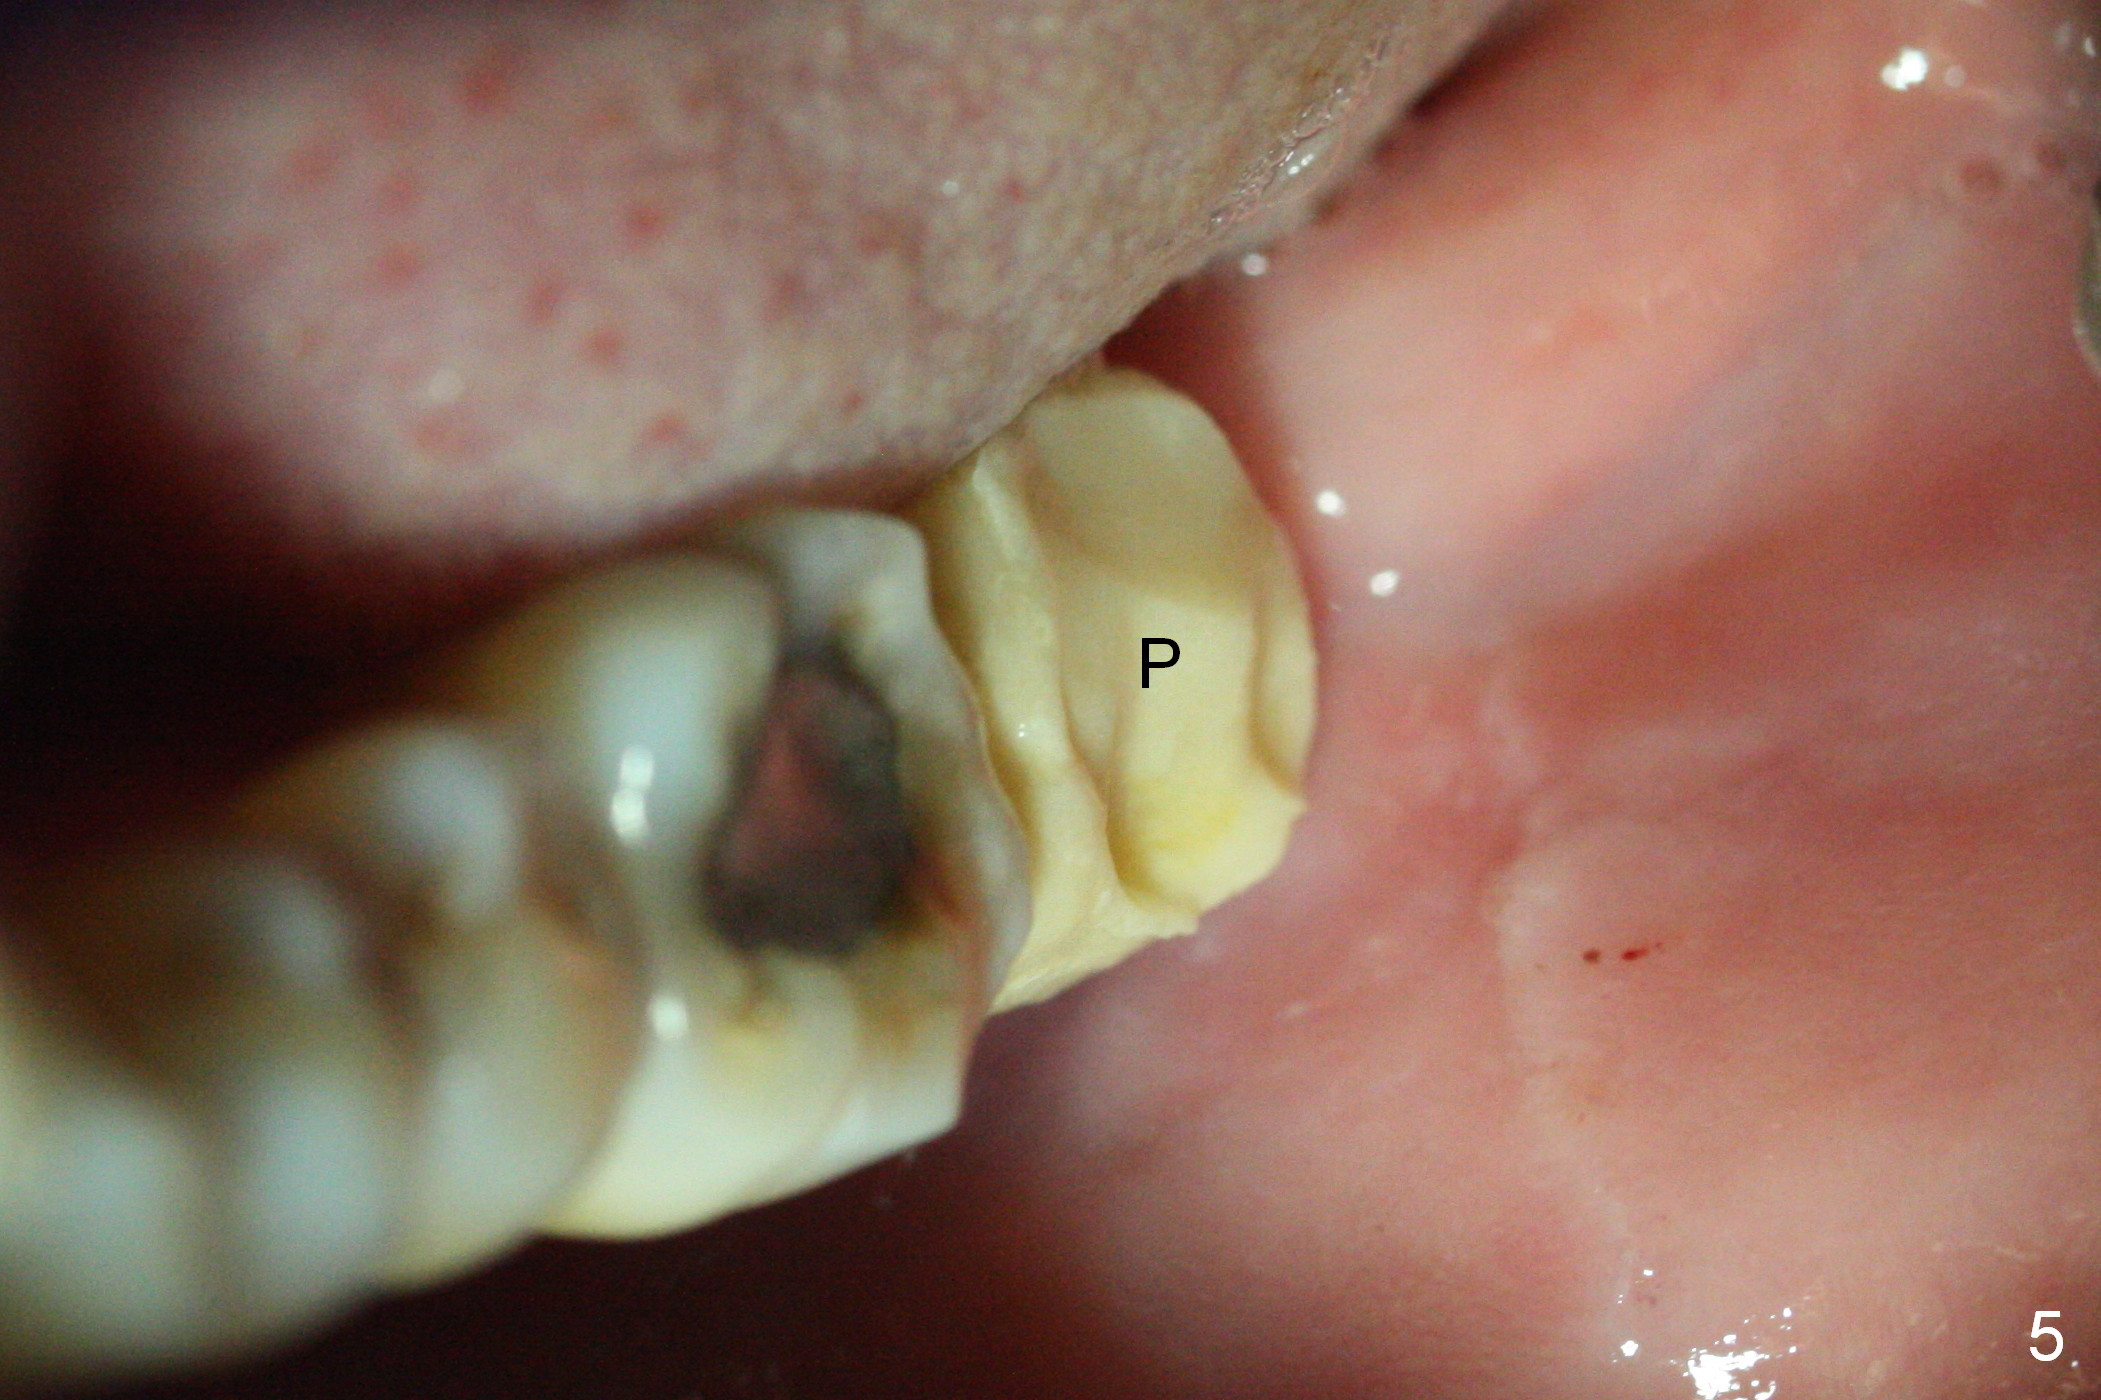

A 50-year-old man has lost the tooth #18 for 10 years; the opposing tooth (#15) has been supraerupted in the last 6 years (Fig.1,2). Mini-implants are placed to intrude the tooth #15 (Fig.2 arrow), instead leading to distalization in 4 months (Fig.3 arrow). Segmental orthodontic appliances are placed with noncompliance. Five months post implant placement at #18, a provisional (Fig.5 P) is fabricated with intentional supraocclusion. In 4 months, the marginal ridges of the teeth #14 and 15 are at the same level (Fig.4). To prevent the 2nd molar from distalization, keep the third molar if present.